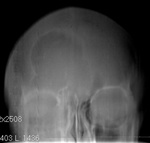

Интересная картинка. Пазуха или опухоль?

будь МУКОцеле - было бы затенение соответствующей пазухи, и в боковой проекции выбухание кнаружи. Думаю, вариант развития нормы.

На вариант развития развития пазухи больше похоже.

Затемнено-не затемнено, санирована - не санирована, без подбородочно носовой проекции не скажешь. По прямому, похоже, что левая в/ч пазуха затемнена.

Признаки прерывания кортикального слоя?

Могу предположить арахноидальную киту.